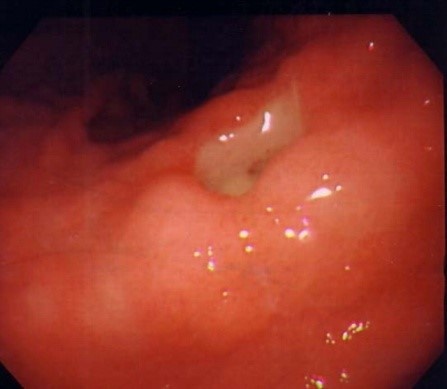

Диагноз язвенной болезни желудка и двенадцатиперстной кишки ставится на основании эндоскопического и/или рентгенологического исследования этих органов.

1. **Фиброгастроскопия** — осмотр слизистой оболочки желудка и двенадцатиперстной кишки с помощью специального прибора — фиброгастроскопа. Это исследование должно проводиться неоднократно, чтобы контролировать процесс заживления язвенного дефекта на слизистой. Во время эндоскопии обязательно выполняются биопсии с краев язвы для проведения гистологических исследований, что позволяет исключить рак.